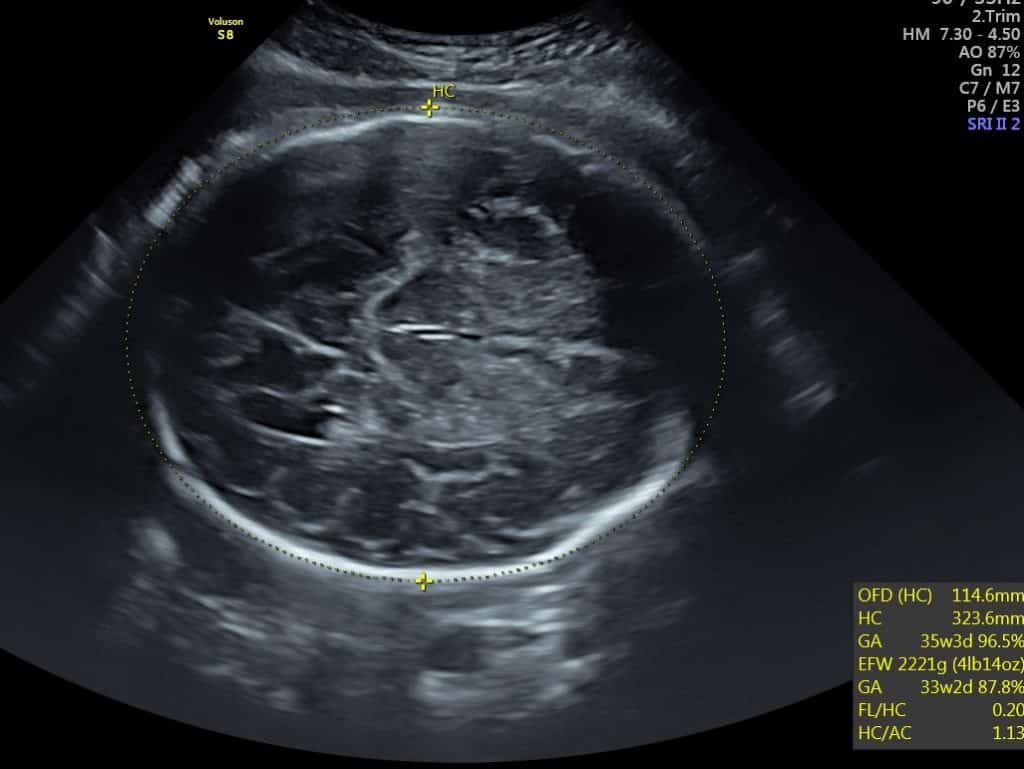

Our specialist sonographer will measure the circumference of baby’s head and the abdominal circumference. They then move on to measure baby’s femur length. To make sure the details are accurate, they will measure each body part 3 times. We will also provide you with an estimated fetal weight, in grams. You’ll receive photo prints, a diagnostic report plus more to take away.

This scan is all in 2D; the sonographer will move onto taking the measurements of baby and will provide the information to your personal scan assistant, to be added to your well-being report.